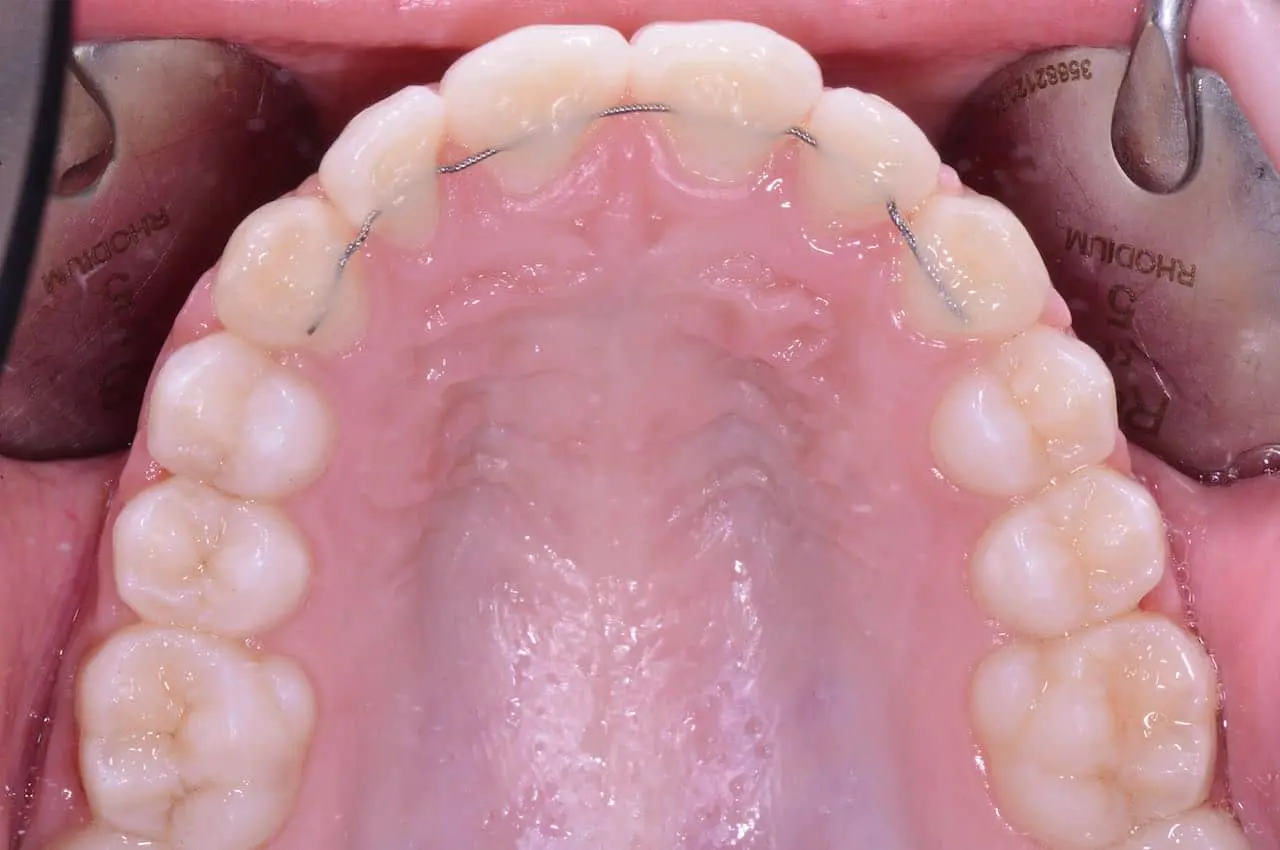

Retainers Fissi

I retainers fissi sono dispositivi permanenti che vengono incollati sulla superficie interna dei denti, solitamente sui denti anteriori. Sono progettati per rimanere in posizione per un lungo periodo, senza la necessità di essere rimossi dal paziente.

Come Funzionano i Retainers Fissi

Il retainer fisso è costituito da un filo metallico che viene fissato dietro gli incisivi superiori o inferiori. Il filo viene incollato utilizzando una resina speciale e può essere nascosto dietro i denti, risultando quasi invisibile. Il vantaggio principale di questo tipo di retainer è che non richiede alcuna collaborazione da parte del paziente, poiché rimane fisso e non può essere rimosso.

Vantaggi dei Retainers Fissi

- Mantenimento permanente: Non c’è bisogno di ricordarsi di indossarlo, poiché è fissato ai denti e funziona senza interruzioni.

- Comodità: Una volta installato, il retainer fisso è molto comodo e non interferisce con le normali funzioni della bocca, come parlare o mangiare.

- Efficacia: È ideale per mantenere la posizione dei denti a lungo termine, evitando la recidiva ortodontica.

Svantaggi dei Retainers Fissi

- Igiene orale più complessa: Poiché il filo è attaccato ai denti, è più difficile pulire correttamente gli spazi interdentali. Il filo interdentale può essere utilizzato con uno scovolino o uno spazzolino interdentale per garantire una buona pulizia.

- Visite regolari: È necessario visitare regolarmente l’ortodontista per verificare lo stato del retainer e per controllare che non si stacchi o si danneggi.